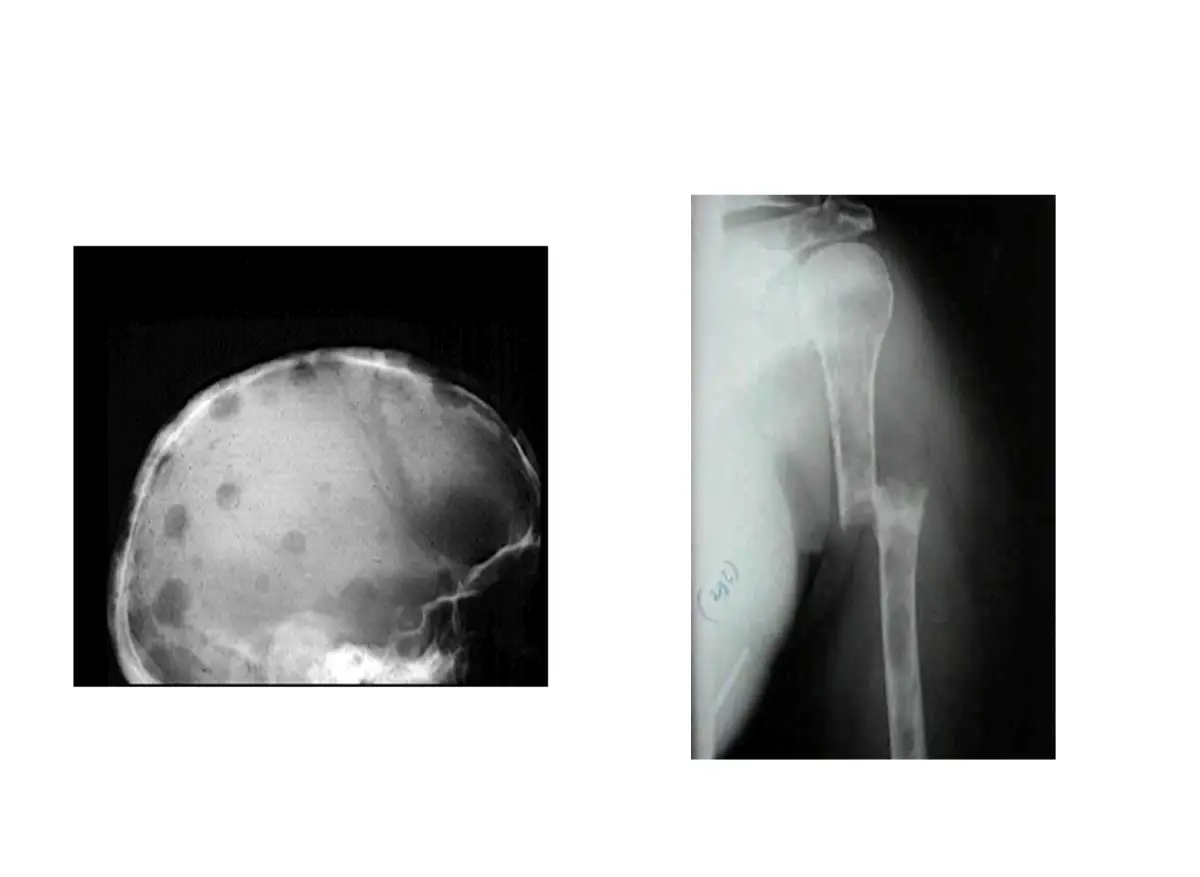

一位 62歲男性因跌倒就醫,實驗室檢查顯示 Hb 7.6 g/dL , MCV 85 fL , platelet 120,000/μL 。下圖分別為其骨髓抹片及X光,其診斷最可能為下列何者?

- 顱骨側位 X 光:顱骨可見多發圓形、邊緣清楚的透亮病灶(punched-out lytic lesions),大小不一,無骨質反應(periosteal reaction),與多發性骨髓瘤典型「雨滴狀」透亮區相符(emedicine.medscape.com)。

- 肱骨 X 光:肱骨幹段見